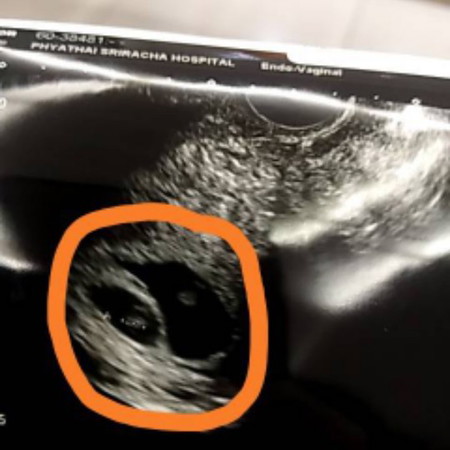

คุนหมอบอกเจอถุงตั้งครรภ์2ถุงค่ะ

ถ้ามีตัวอ่อนที่เติบโตตามปกติทั้งสองถุง ก็ได้แฝดจ๊ะ ยินดีด้วยนะจ๊ะ